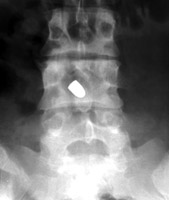

Tumbling Bullet Sign

Two sets of frontal and lateral radiographs, separated only by time, which reveal the "tumbling bullet sign"--which is simply a bullet which changes its location and orientation within a solitary bone cyst. This sign serves two purposes. It is documentation of the evolution of a solitary bone cyst as a corollary of trauma, and reveals the free movement of the foreign body within the confines of the lesion establishing its cystic rather than solid nature. It is similar to the fallen fragment sign.

- Click on the image for a larger versionA - Click on the image for a larger versionB - Click on the image for a larger versionC - Click on the image for a larger versionD